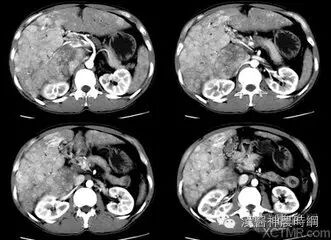

1.超声检查  B超检查用于肝癌诊断具有无损伤、无放射损害、简便、价廉、敏感度高、可重复性等优点。它可显示肿瘤的大小、形状、部位、肿瘤与血管的关系以及肝静脉、门静脉有无癌栓等,其诊断符合率可达90%。B超可检出1~2cm的小肝癌,最小直径为0.5~0.7cm。文献报道高分辨力B超对0.5~2.0cm的肝内微小灶的发现率较高,但定性诊断的准确率仅为58%。

近年国内外均有人采用超声对比剂,如铁或钆等行声学造影,有助于定性诊断和确定病灶大小。原发性肝癌B超图像常显示肝体积增大,病变向肝表面隆起,周围常有声晕等。其回声可表现为低回声型、高回声型和混合回声型。小肝癌常呈低回声型,大肝癌或呈高回声,或高低回声混合,并可见中心坏死液化的无回声区。B超检查可因肺、胃等器官遮盖存在盲区,造成遗漏病变,如右膈下、左外叶上段等。微小病变位于肝实质深部并伴有严重肝硬化时,常难以辨认。另外与操作者的经验和检查是否细致均有关。